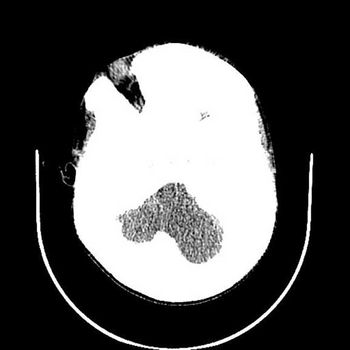

Case History: A 12-year-old male complaining of skull expansion, facial deformity, nasal stuffiness, proptosis and visual impairment.